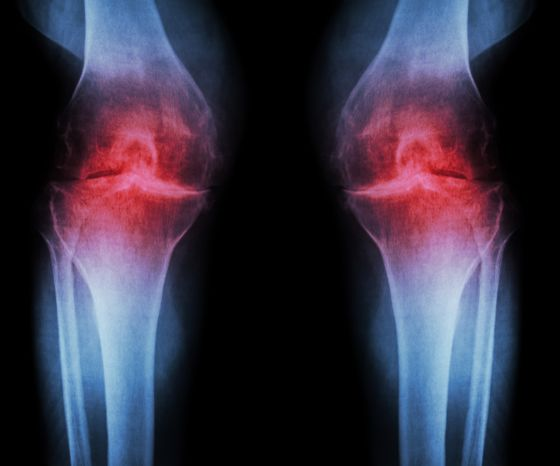

影像学检查指南:X光、MRI到底能看出什么“名堂”?

骨关节炎的诊断方法与标准

骨关节炎的诊断看似复杂,但只要按照规范的步骤,结合临床表现、影像学检查、实验室检查等多方面信息,就能做出准确的诊断。 早诊断、早治疗,配合合理的营养和运动干预...